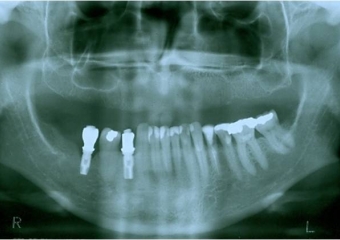

Raio x após enxerto de ilíaco

Raio x após instalação dos implantes superiores Cone Morse